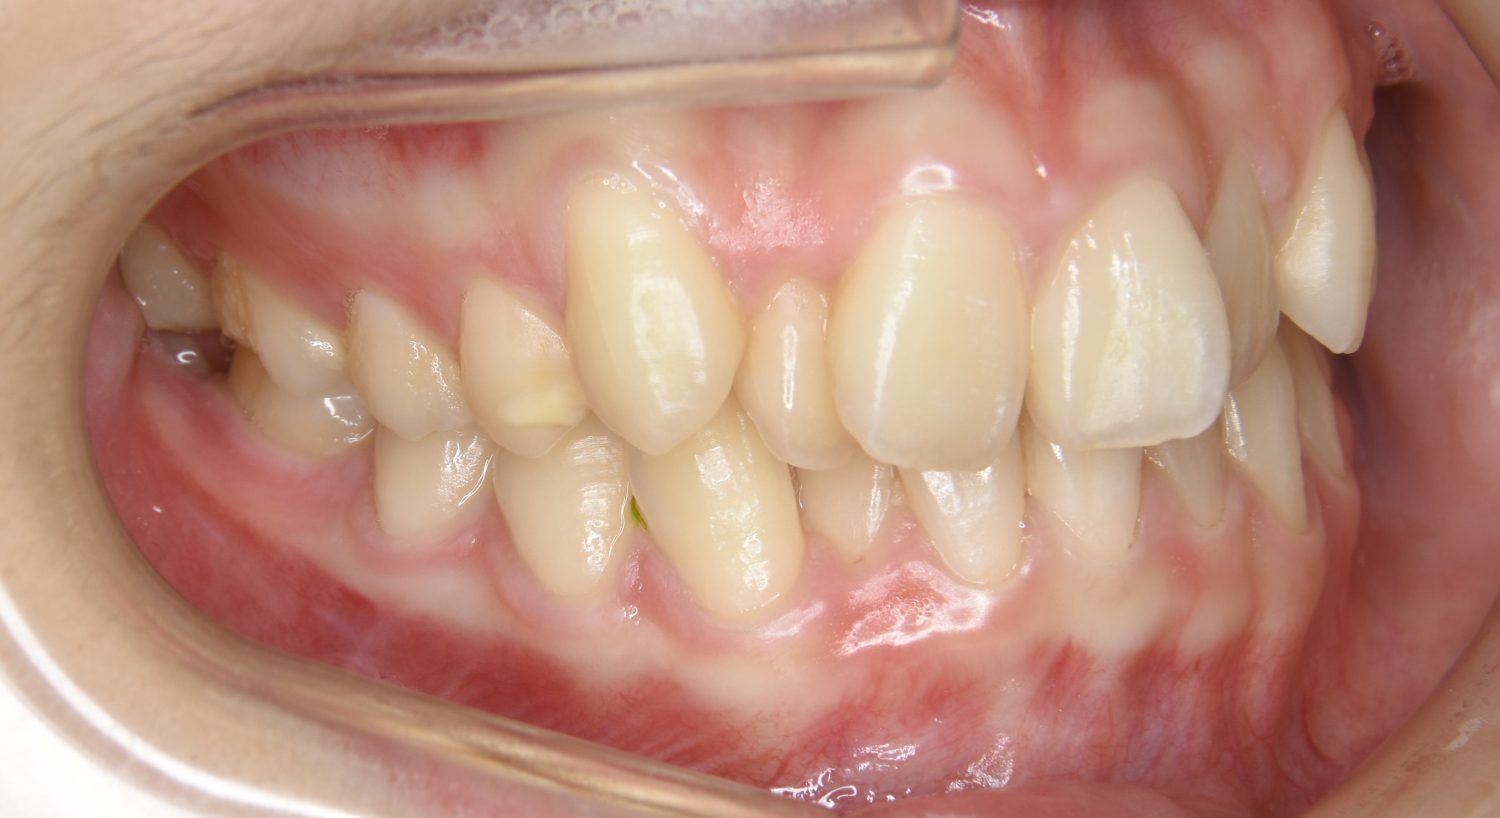

叢生の症例紹介①

Before

After

主訴

前歯のガタガタが気になる。

治療内容

上顎左側第一小臼歯を抜歯し、アライナー(インビザライン)にて治療を行いました。

左上の側切歯が完全に内側に入り込んでいる状態でした。左上の第一小臼歯のみ抜歯を行い治療を行うことで機能面および審美面を改善しました。